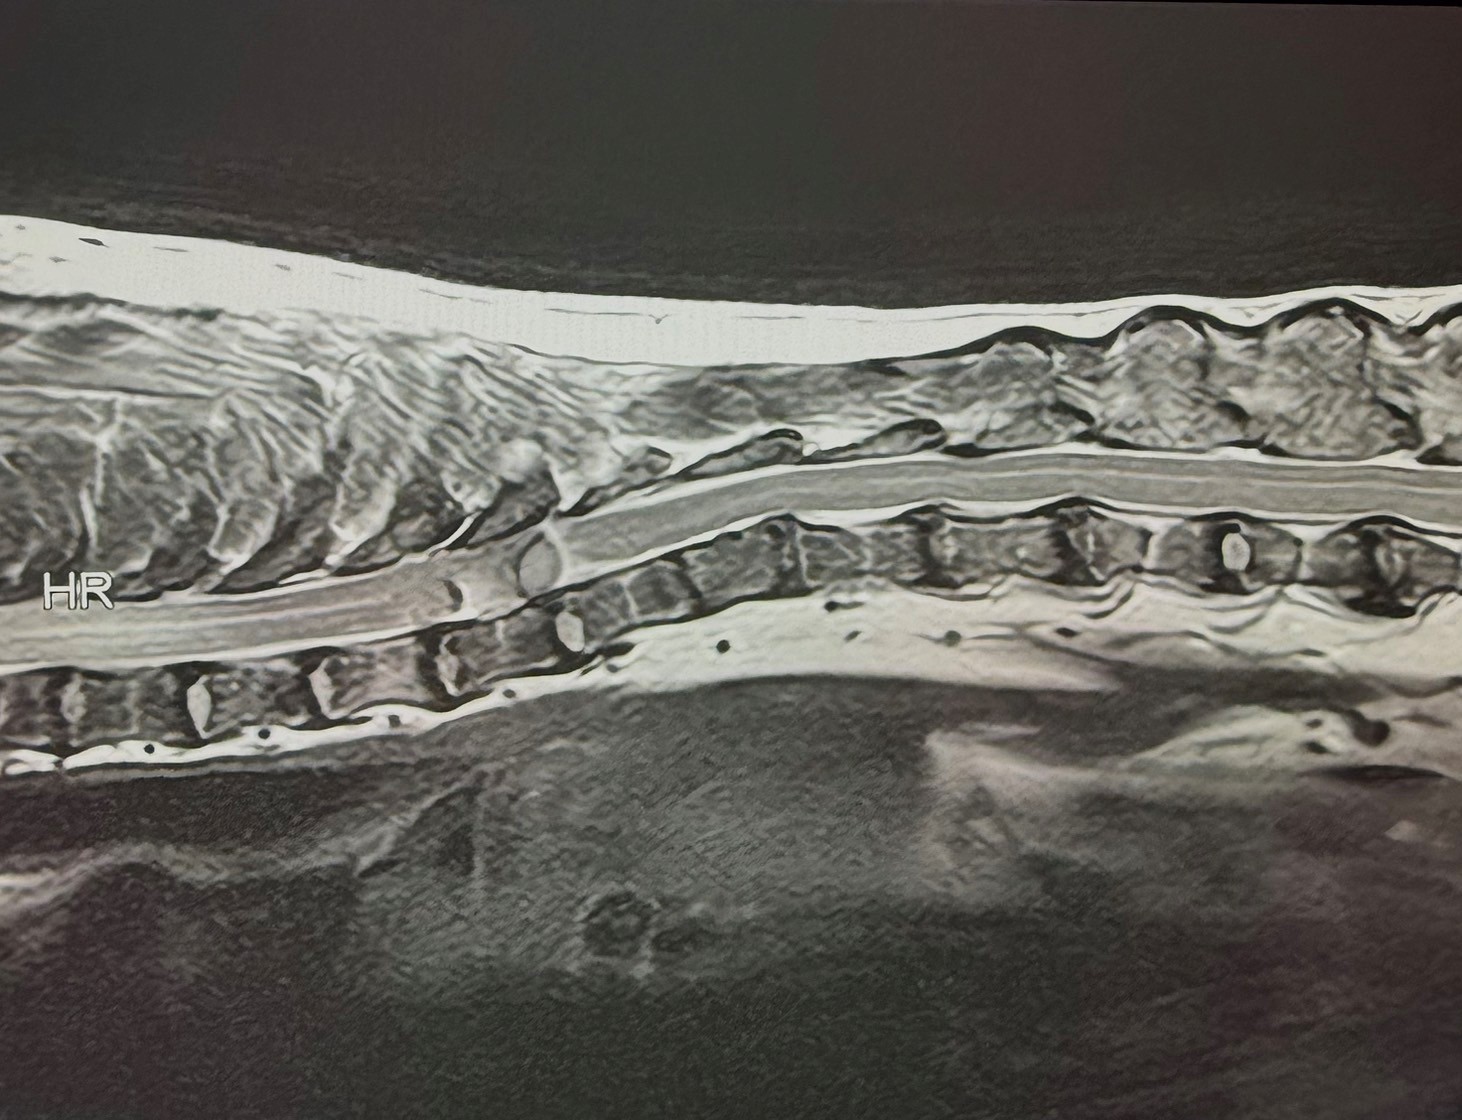

犬の腰部椎間板ヘルニアに対し片側椎弓切除術を実施した1例の画像

犬の腰部椎間板ヘルニアに対し片側椎弓切除術を実施した1例

• 画像診断科

• 脳神経科

• 診断

• 手技

• 症例